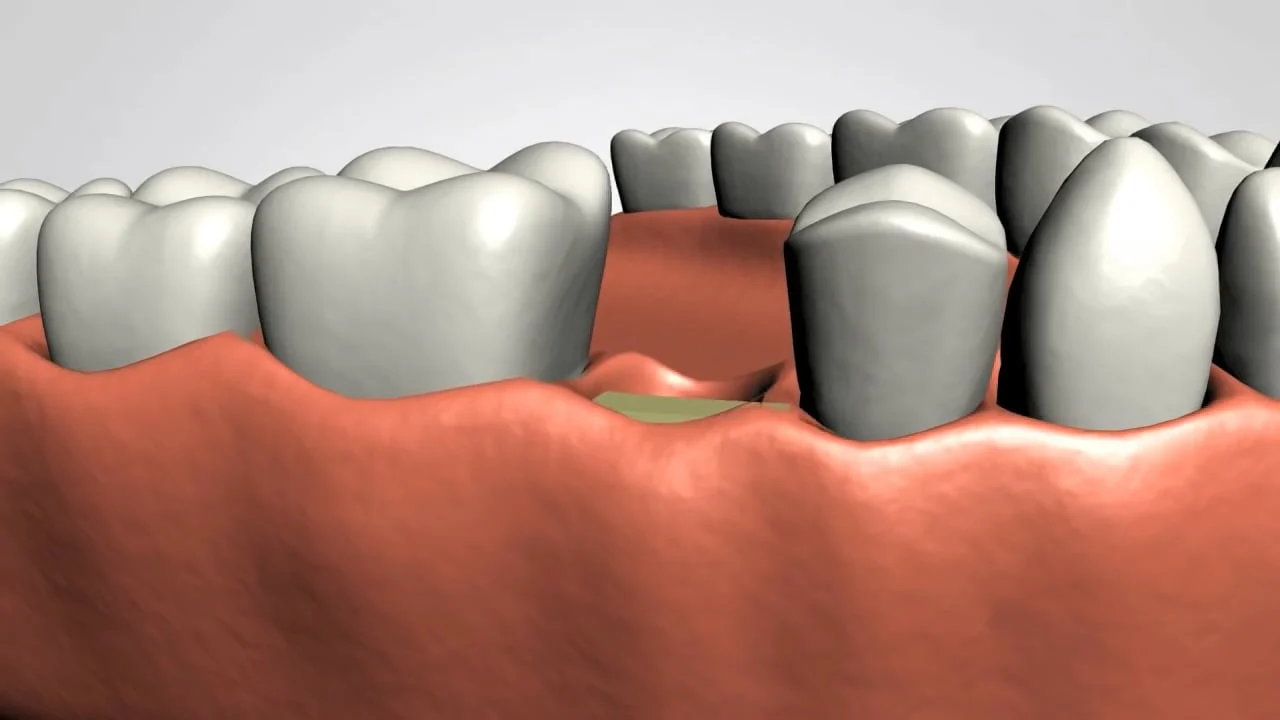

If you have a missing tooth, the most popular option are dental implants. Cosmetic dentistry in Tampa, FL, is a remarkable way to replace missing teeth and support a dental crown, dental bridge, or even a partial denture. The practice of implant dentistry has many people interested lately because of the remarkable benefits dental implants offer. Drs. Richard and Jennifer Kernagis has significant experience as implant dentists in FishHawk. If you need a dental implant in Tampa, our doctors can place your implant in a way that will help you feel confident and satisfied.

Implant dentistry has come so far and has solved so many of the problems people have had with missing teeth. Some common benefits of implant dentistry our patients in Tampa experience are:

Once your dental implant is placed, you most likely will forget it isn’t your real tooth. You can laugh, talk, chew, and eat just like normal. In fact, if the tooth has been missing for a while, you may find that your mouth works better than before!

Our doctors, trained in dental implants, will place tooth implants that look like real teeth, the same color as your natural teeth. You can smile with confidence and may even want to smile more often!

A tooth implant is exceedingly strong. Though you know, it’s a tooth implant and durable. It’s like a brand new tooth,

right where your old tooth used to be.